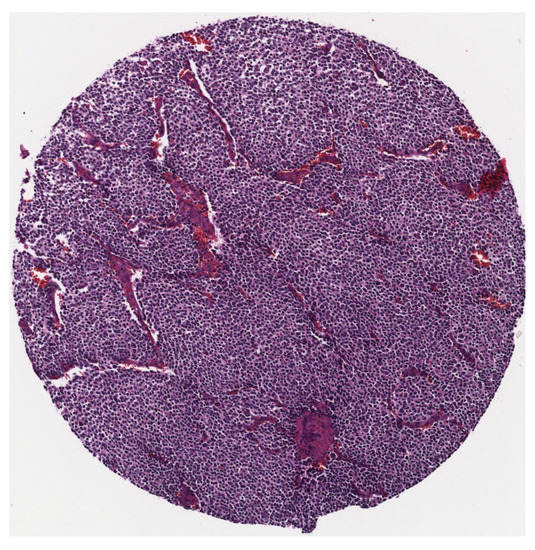

As there is no public and available dataset in analysis of neuroblastic tumours we constructed a dataset which consists of images from neuroblastic tumours from The Tumour Bank of the Kid’s Research Institute at The Children’s Hospital at Westmead, Sydney, Australia. All the specific details of patients were removed from the dataset and a de-identified dataset was used in this research. The initial dataset was generated from cancer tissue biopsy slides and consisted of images of H&E stained tissue microarrays (TMA) of neuroblastic tumours. We used six TMA slides and seven whole sections representing 125 patients. Each TMA slide contains from 20 to 40 cores of neuroblastic tumour. Samples of TMA slide containing cores of different neuroblastic tumours are shown in Figure 2 and Figure 3, respectively. The diameter of TMA cores is 1.2 mm, stained with H&E and cut at 3 μ m thickness. Although most images belong to different patients, some of them are duplicates. Our constructed dataset is much larger in terms of patients and images than the datasets used by Tafavogh et al. [12] and Kong et al. [11].

All collected tissue samples were classified as undifferentiated neuroblastoma, poorly-differentiated neuroblastoma, differentiating neuroblastoma, ganglioneuroblastoma, or ganglioneuroma by pathologists. Representative images in the categories are shown in Figure 4.

Figure 3. A sample of a single tumour.